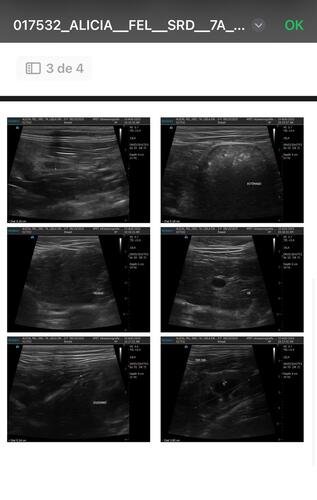

Após vários exames de ultrassom e medicação para dilatar os ureteres nos quais ela tem as pedras, como tentativa de não submetê-la á cirurgia, não tivemos sucesso. Sendo realmente necessária a cirurgia para remoção das pedras.

A Alicia foi diagnosticada com doença renal crônica e está enfrentando um quadro muito grave: ela tem muitas pedras nos dois rins e uma obstrução séria no ureter direito, o que está comprometendo sua saúde de forma crítica.O único caminho possível para salvá-la é através de uma cirurgia delicada chamada "ureter bypass", que custa entre R$ 15 mil e R$ 25 mil reais, incluindo todos os gastos como internação, medicamentos, alimentação, exames, transporte entre outros gastos — um valor que está completamente fora das minhas possibilidades no momento.